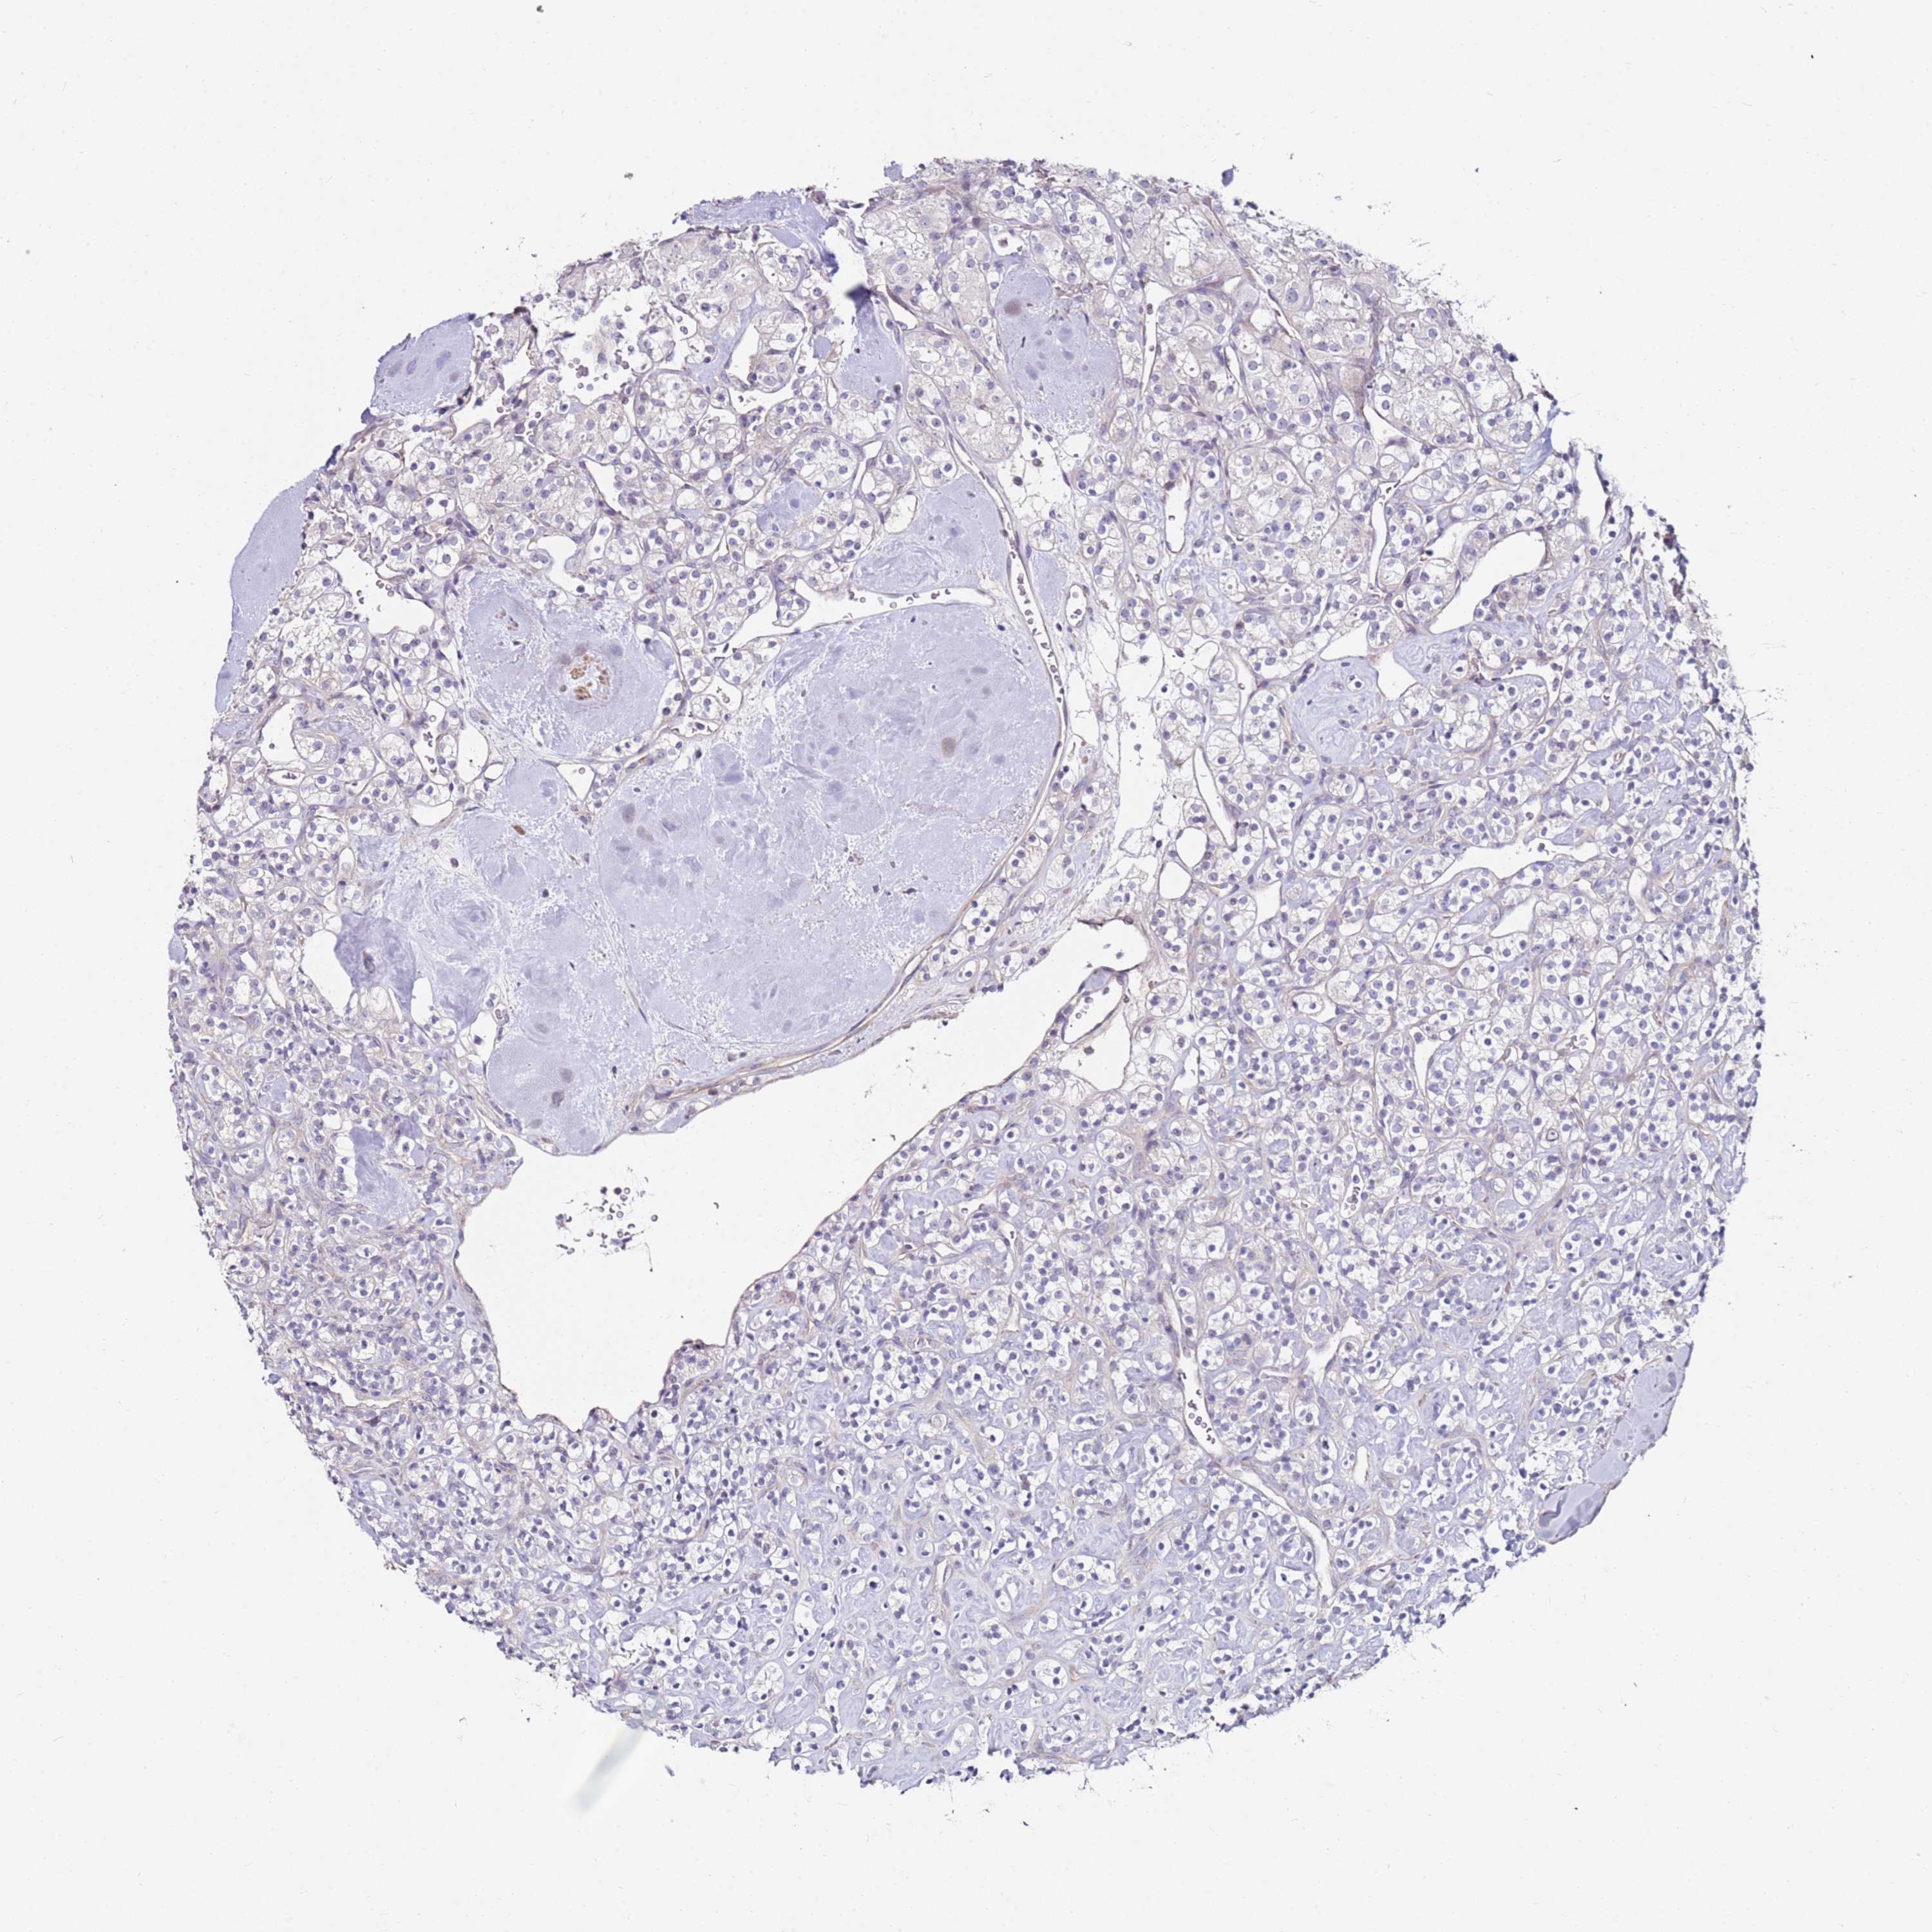

KIDNEY RENAL CLEAR CELL CARCINOMA (TCGA) - Interactive survival scatter ploti

The Survival Scatter plot shows the clinical status (i.e. dead or alive) for all individuals in the patient cohort, based on the same data that underlies the corresponding Kaplan-Meier plots. Patients that are alive at last time for follow-up are shown in blue and patients who have died during the study are shown in red.

The x-axis shows the expression levels (FPKM) of the investigated gene in the tumor tissue at the time of diagnosis. The y-axis shows the follow-up time after diagnosis (years). Both axes are complimented with kernel density curves demonstrating the data density over the axes. The top density plot shows the expression levels (FPKM) distribution among dead (red) and alive patients (blue). The right density plot shows the data density of the survived years of dead patients with high and low expression levels respectively, stratified using the cutoff indicated by the vertical dashed line through the Survival Scatter plot. This cutoff is automatically defined based on the FPKM cutoff that minimizes the p-score. The cutoff can be changed by dragging the vertical line or by entering a cutoff value in the square labeled "Current cut-off".

Under the Survival Scatter plot the p-score landscape (black curve; left axis) is shown together with dead median separation (red curve; right axis). Dead median separation is the difference in median mRNA expression between patients who have died with high and low expression, respectively. It is calculated as follows: median FPKM expression of dead patients with high expression - median FPKM expression of dead patients with low expression. This is intended to aid the user in visually exploring custom cutoffs and the associated p-scores and dead median separation.

Individual patient data is displayed and can be filtered by clicking on one or more of the category buttons on the top of the page. Categories describing expression level and patient information include: high, low, alive, dead, female, male and tumor stages. The scale of the x-axis can be toggled between linear and log-scale by clicking on the "x log" button. Mouse-over function shows TCGA ID, patient information and mRNA expression (FPKM) for each patient.

& Survival analysisi

Kaplan-Meier plots summarize results from analysis of correlation between mRNA expression level and patient survival. Patients were divided based on level of expression into one of the two groups "low" (under cut off) or "high" (over cut off). X-axis shows time for survival (years) and y-axis shows the probability of survival, where 1.0 corresponds to 100 percent.

RARS2 is not prognostic in Kidney Renal Clear Cell Carcinoma (TCGA)

Best expression cut offi

Based on the FPKM value of each gene, patients were classified into two groups and association between prognosis (survival) and gene expression (FPKM) was examined. The best expression cut-off refers the FPKM value that yields maximal difference with regard to survival between the two groups at the lowest log-rank P-value. Best expression cut-off was selected based on survival analysis .

When clicking on this number, the vertical dashed line indicating cut-off, the interactive survival plot, and the Kaplan-Meier curve will be adjusted to show results based on the best expression cut-off.

: 15.59

Median expressioni

Median expression refers to the median FPKM value calculated based on the gene expression (FPKM) data from all patients in this dataset. When clicking on this number, the vertical dashed line indicating cut-off, the interactive survival plot, and the Kaplan-Meier curve will be adjusted to show results based on the median expression.

: N/A

Median follow up timei

Median follow up time refers to the median time (years) after diagnosis with this type of cancer, based on clinical data from all patients in this dataset.

P scorei

Log-rank P value for Kaplan-Meier plot showing results from analysis of correlation between mRNA expression level and patient survival.

N/A

5-year survival highi

5-year survival for patients with higher expression than the expression cutoff.

For melanoma and glioma, 3-year survival is shown.

5-year survival lowi

5-year survival for patients with lower expression than the expression cutoff.

TCGA RNA samplesi

RNA-seq data is reported as average FPKM (number Fragments Per Kilobase of exon per Million reads), generated by the The Cancer Genome Atlas (TCGA) .

Normal distribution across the dataset is visualized with box plots, shown as median and 25th and 75th percentiles. Points are displayed as outliers if they are above or below 1.5 times the interquartile range. FPKM values of the individual samples are presented next to the box plot.

Average pTPM 22.8

Number of samples 521